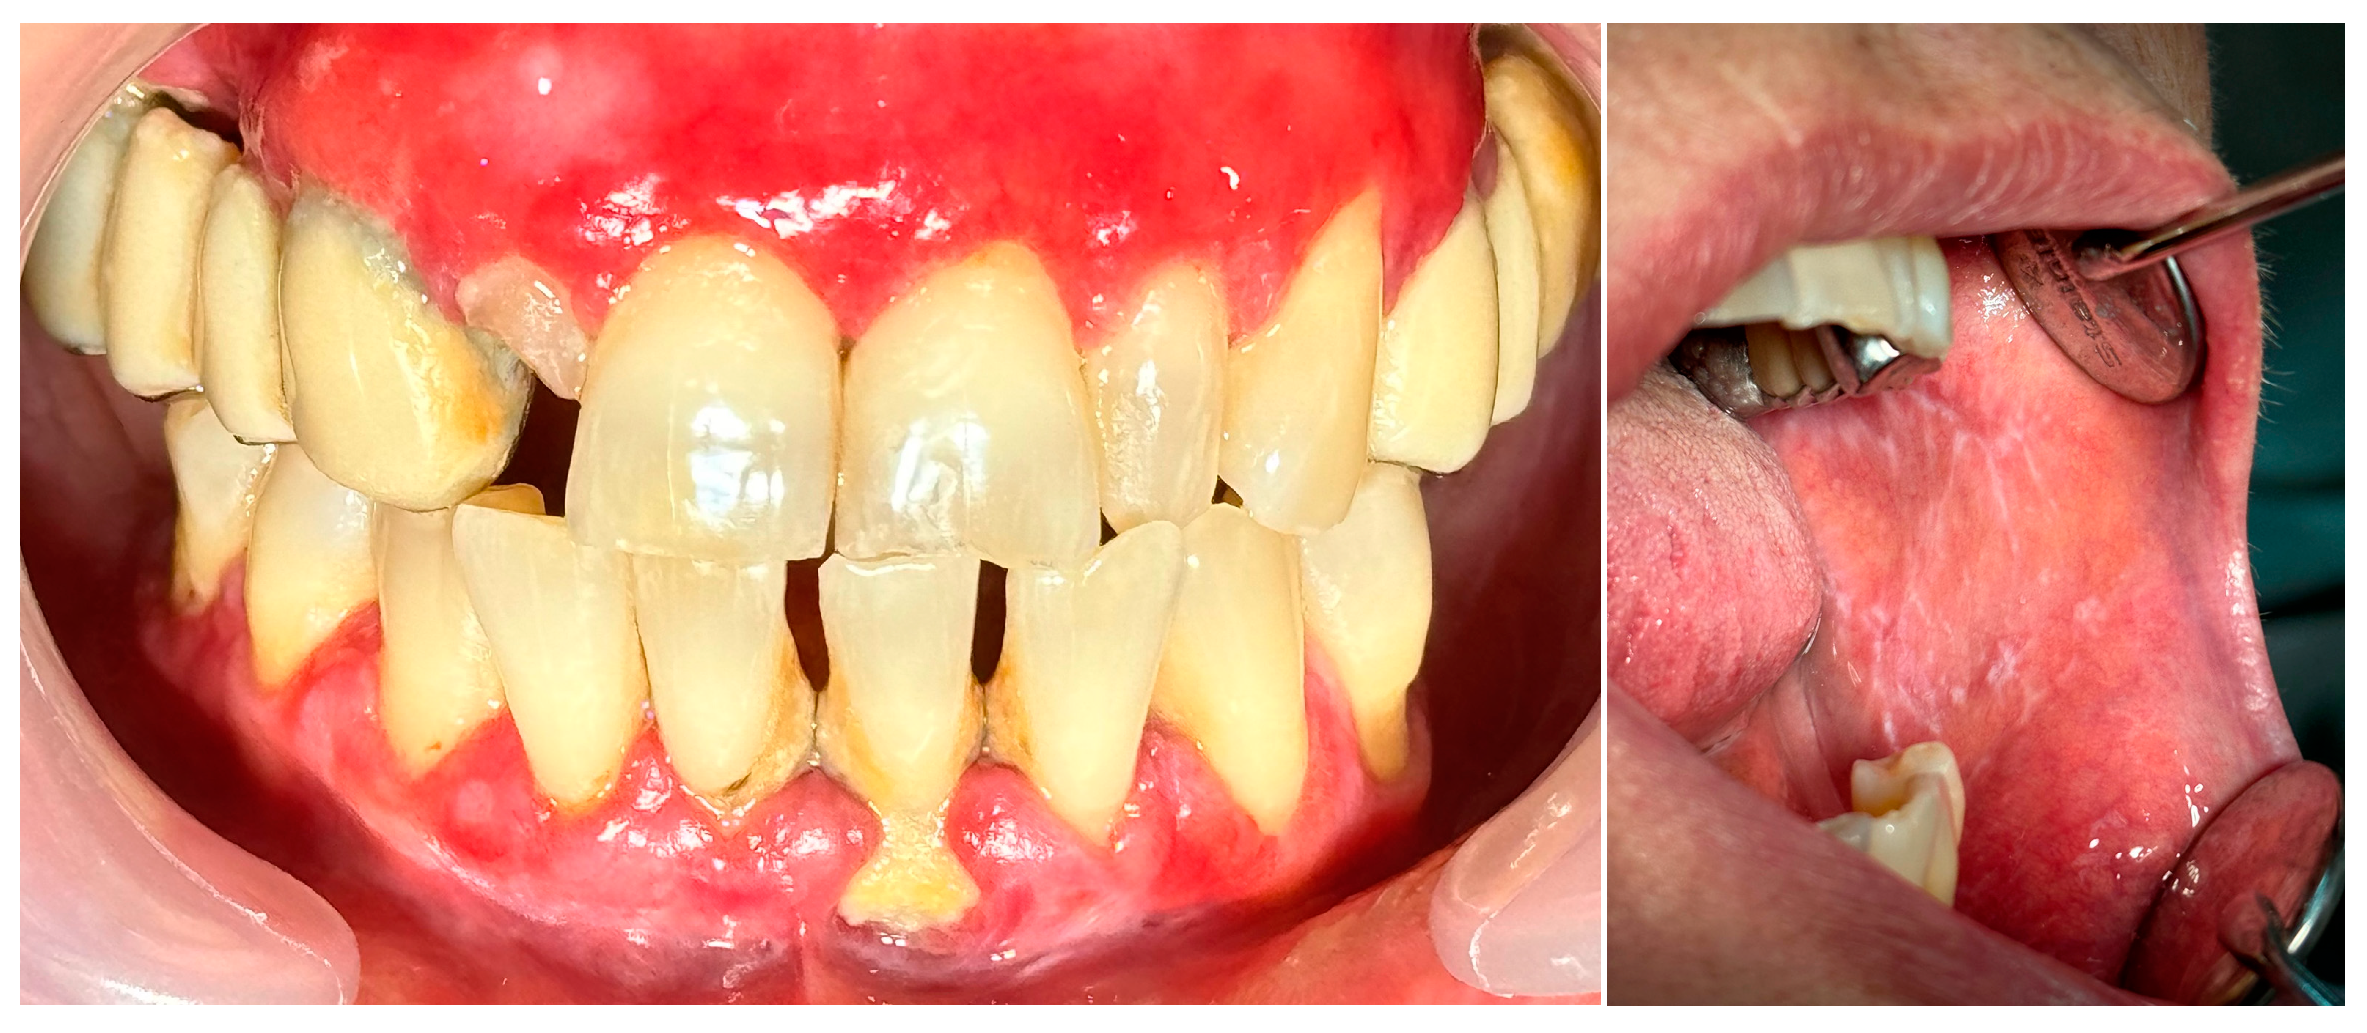

2.2. Clinical Case 2—Pemphigus Vulgaris (PV)